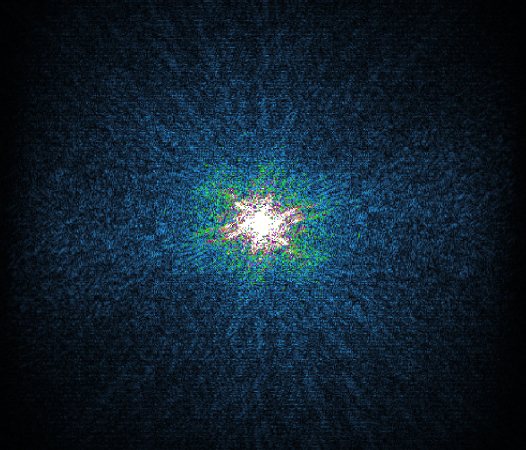

In the example below, only one fifth of the required MR radiofrequency signals is recorded. This results in a five times faster acquisition, with a subsampled k-space (top left) and inherent image artifacts after standard reconstruction (top right).

Basic compressed sensing principle

The Compressed SENSE reconstruction then uses iterative, knowledge-based algorithms to fill in the empty lines in k-space (bottom left). This removes the artifacts while keeping the final image fully consistent with the acquired data (bottom right). *Compared to Philips MR exams without Compressed SENSE